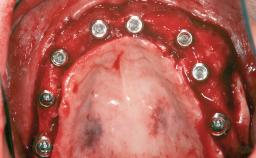

Autologous Block Graft and Guided Bone Regeneration (GBR) for Horizontal Ridge Augmentation in the Posterior Mandible

An 18-year-old man was referred for implant therapy in the posterior mandible to the Department of Oral Surgery and Stomatology (University of Bern, Switzerland). He was healthy and did not smoke. Tooth 35 was congenitally missing, involving a single-tooth edentulous space that offered an adequate mesiodistal dimension for implant placement but exhibited a typical pattern of buccal flattening. A panoramic radiograph was obtained, which revealed a sufficient vertical bone height above the mandibular canal and a normal bone structure in the edentulous area.

Bone Augmentation Horizontal|Staged

Augmentation Materials Autogenous chips|Autogenous block(s)|Xenogenous|Membrane

Bone Volume Deficient horizontally, requiring prior grafting